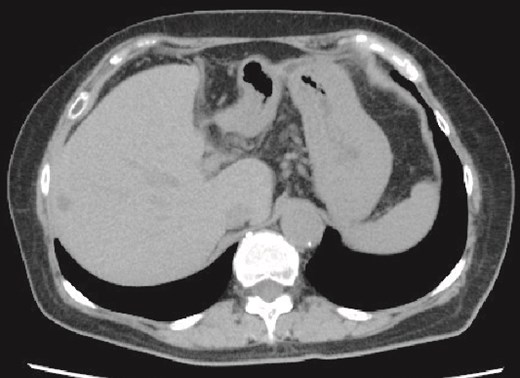

On day 13 of admission, an upper gastrointestinal contrast examination showed no obvious communication between the hepatic cyst and the duodenum (Fig. 2a). On day 20, CT showed that the hepatic cyst had tended to shrink but had not disappeared; in addition, the cyst wall had thickened (Fig. 2b). The CT also identified a low-density area between the hepatic cyst and the duodenum, which we suspected was a fistulous tract between them (Fig. 2c). On day 21, an upper gastrointestinal endoscopy revealed an ulcer scar at the anterior aspect of the duodenum bulb (Fig. 2d). A biopsy of the ulcer scar tissue revealed no malignancy.

The upper gastrointestinal contrast examination findings on day 13 of the patient’s hospital admission. (a) There was no obvious fistulous tract between the hepatic cyst and the duodenum. arrowheads: The stomach, arrowheads: The duodenum. arrow: The 7Fr pig-tail catheter. (b, c) Enhanced CT images findings on 20 day of admission. (b) Axial section. A shrunken hepatic cyst with a thickened cyst wall was observed. Dotted line: The large hepatic cyst. Arrowheads: The 7Fr pig-tail catheter. (c) Coronal section. A a low-density area was observed between the hepatic cyst and the duodenum, suspected of being a fistulous tract. Arrows: The low-density area between the hepatic cyst and the duodenum. Arrowheads: The 7Fr pig-tail catheter. (d) An upper gastrointestinal endoscopy on admission day 21 showed an ulcer scar at the anterior aspect of the duodenum bulb without obvious fistulous orifice. Arrowheads: The ulcer scar at the anterior aspect of the duodenum bulb.